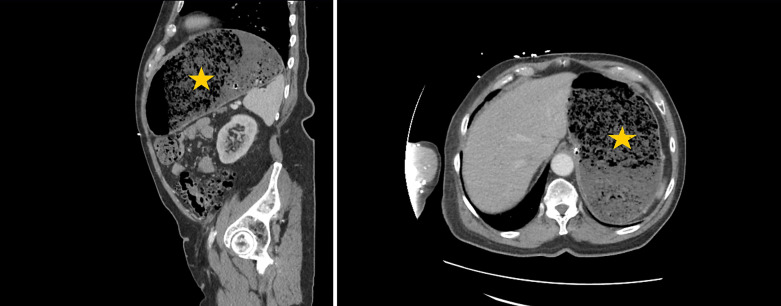

简介急性胃扩张(AGD)是由气体、胃分泌物或食物堆积引起的胃部大量膨胀。AGD 是一种放射学诊断,没有明确的发病机制,由于缺乏明确的诊断标准和医生的认识,AGD 经常被误诊:在本病例系列中,我们描述了 4 位 AGD 患者的临床表现和治疗结果。其中三名(75%)患者为女性,一名(25%)患者为男性。患者年龄从 53 岁到 84 岁不等,平均年龄为 73.5 岁。腹痛、恶心和呕吐是最常见的主诉。两名患者(50%)患有癌症,一名患者(25%)患有后天性十二指肠狭窄,第四名患者出现回肠梗阻:AGD是一种外科急症,死亡率高达50%-100%;因此,及时诊断和治疗至关重要。在此,我们描述了本院诊断和处理的一系列 AGD 病例。我们旨在提高人们对这一致命但未得到充分认识的临床实体的认识。

Introduction: Acute gastric dilatation (AGD) is a massive distension of the stomach caused by the accumulation of gas, gastric secretions, or food material. AGD is a radiological diagnosis with no clear etiopathogenesis and is often misdiagnosed owing to a lack of clear diagnostic criteria and physician awareness.

Case presentation: In this case series, we describe the clinical presentations and outcomes of 4 patients with AGD. Three (75%) of the patients were female, and one (25%) was male. The patients' ages ranged from 53 to 84 years, with an average age of 73.5 years. Abdominal pain, nausea, and vomiting were the most frequently reported complaints. Two (50%) patients had cancer, one (25%) had an acquired duodenal stenosis, and the fourth patient experienced an ileus.